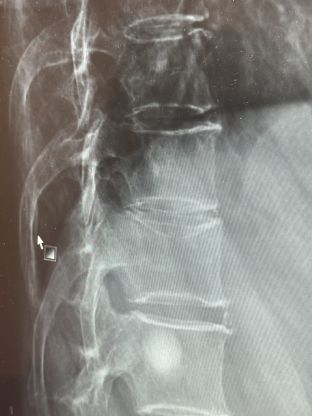

先日の東京駅でのアクシデントで、背骨が凹んでしまい酷い痛みが続います。3日間寝込みようやく整形外科へ行きレントゲンを撮った結果、写真の様に背骨の1箇所が凹んでおりました。回復次第また出勤いたしますので、その際はどうぞ宜しくお願い致します